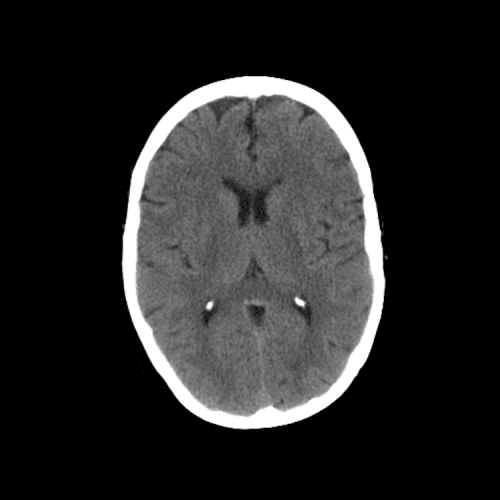

Non-traumatic Head CT Cases

Classic Cases

Includes classic examples of cases commonly seen on call.

Lacunar infarct

Case #7